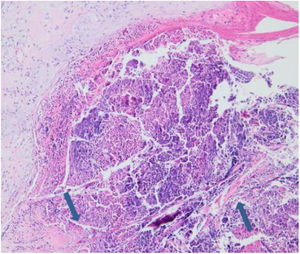

Laboratory results of complete hemogram, blood sugar, liver, and kidney function tests were found to be within normal limits. Histopathological evaluation of a representative skin lesion taken from the left leg showed acanthosis, basket weave orthokeratosis, increased number of vessels in the superficial dermis, and perivascular and interstitial inflammatory infiltrate with erythrocyte extravasation. Punched-out ulceration with cellular debris was observed in the crateriform invagination and transepidermal elimination of collagen fibers (Figs. 4 and 5). ARPC was diagnosed based on the clinical and histological findings and the onset of the disease at the age of 75 years. Treatment with oral acitretin 25mg/day was planned; however, the patient was lost to follow-up. Later, during a control visit to our clinic, an excellent response to gabapentin 300mg/day and topical doxepin cream for one month was observed in the patient; these medications were prescribed in another medical center. Meanwhile, a diagnosis of prostate adenocarcinoma was confirmed following prostate biopsy due to elevated serum levels of prostate-specific antigen.